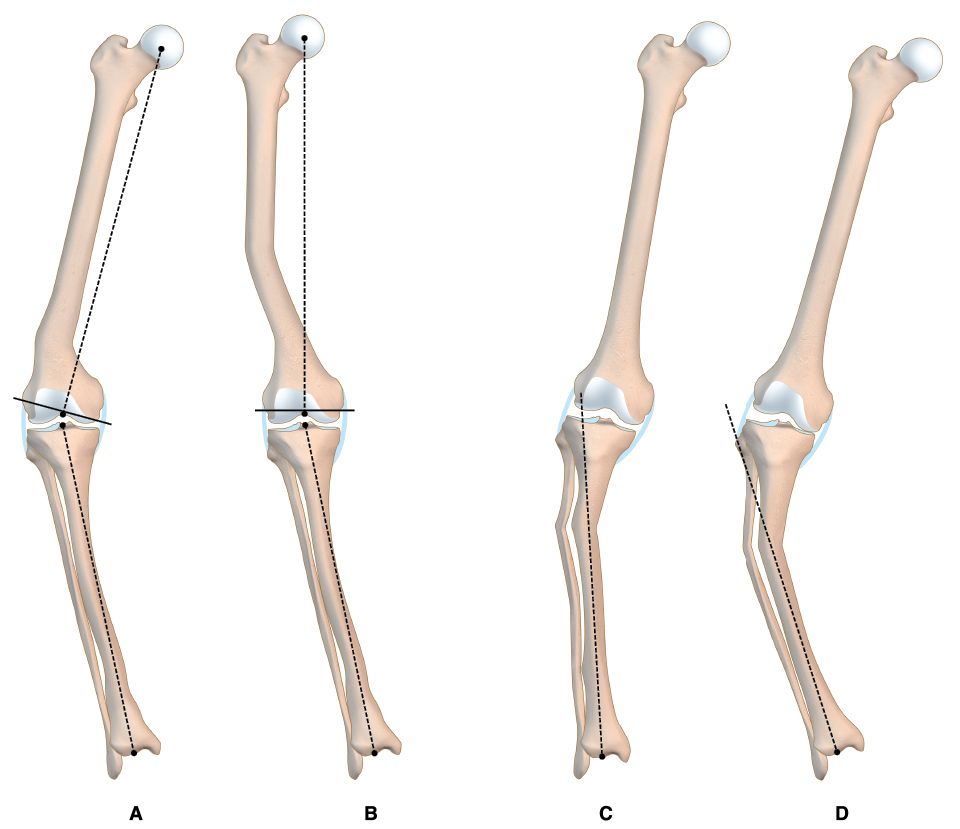

There were 16 varus knees (average intra-articular deformity 9.2°) and 13 valgus knees (average intra-articular deformity 16.6°). The extra-articular deformity was situated in the distal third of the femur in 12 (Figure 1), in the middle third of the femur in 4 patients (Figures 2 & 3), in the proximal third of the tibia in 9 and in the middle third of the tibia in 4 . Regarding the type of deformity, all patients had a coronal deformity, 13 in varus (average 16.3°), 15 in valgus (average 14.4°) and 1 with a medial displacement of the distal femoral epiphysis of 3 cm. (Figure 1). In 8 patients, the deformity was biplanar with alterations in the sagittal plane, 4 in flexion and 4 in extension, with an average of 19.7° and 8° respectively. No patients showed a significant rotational deformity.

In the radiological evaluation it is important that the weight bearing AP view includes the femoral head and the ankle in standing position. If this kind of studies are not available, conventional X-rays may be used, taken separately, with the same magnification to afterwards put together the limb as a puzzle (Figure 2). The knee must be in extension and in neutral rotation. These images will allow to evaluate the effects of the deformity in the final axis of the limb, measure the implant and calculate the necessary bone resections. It is advisable to also have a conventional AP view centred on the joint line.[2], Mullaji Arun, Shetty GM Computer-Assisted Total Knee Arthroplasty for arthritis with extra-articular deformity. J. Arthroplasty. 2009;24(8):1164.[3] Panayiotis JP, Karachaloios T, Themistocleous GS Total knee arthroplasty in patients with pre-existing fracture deformity. Orthopedics. 2007;30(5):373.

There were 2 complications. A 58 y/o male patient with a history of an infected femoral plate and screws and poor soft tissue coverage due to previous surgeries developed a deep infection. Currently, this patient has a cement spacer with antibiotics and a soft tissue expander to improve coverage. A 77 female with a 20º valgus deformity as a sequel of a distal femoral varus osteotomy developed medial instability due to progressive MCL insufficiency, requiring revision to a constrained prosthesis 2 years after the index surgery.